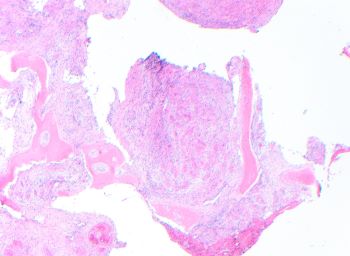

Epithelioid hemangioma of bone most commonly occurs in long tubular bones. The CT scan typically shows lobular architecture with expansile radiolucent, lytic, or cystic-appearing lesion with a narrow transition zone to the normal bone without osteoid matrix. In the head and neck region, epithelioid hemangiomas more frequently arise in skin and soft tissue.

Microscopic sections show a proliferation of well-formed small blood vessels with lobular arrangement and occasionally arranged around small arteries. The small vessels are formed by epithelioid endothelial cells that display abundant eosinophilic cytoplasm and enlarged round nuclei, and normal to low nuclear-to-cytoplasmic ratio; while in more cellular areas the nuclei become elongated. The stroma is hemorrhagic to edematous with mixed inflammatory cells including numerous eosinophils, which may be a clue to the diagnosis in small biopsies.